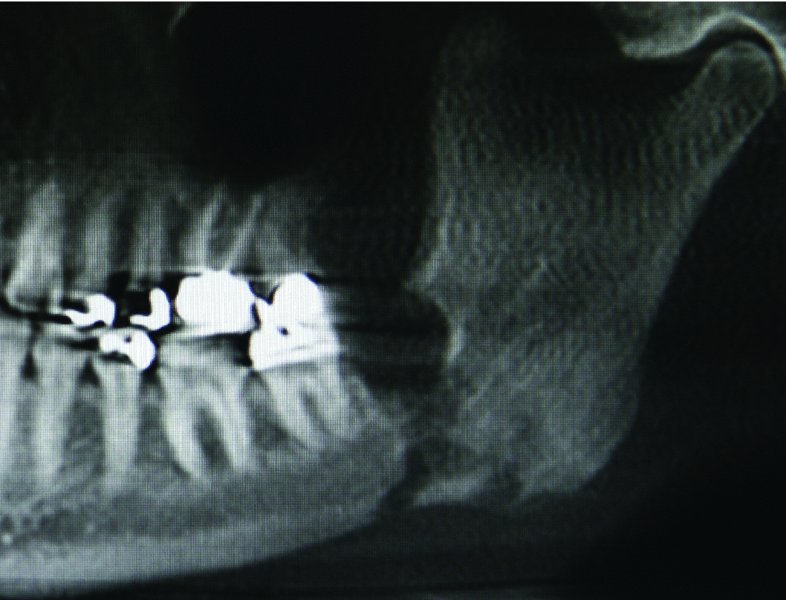

Osteomyelitis After Dental Extraction . In this case report, we review the diagnosis and. Although osteomyelitis is unlikely after a tooth extraction, it's great to understand the possibility and the signs and symptoms of infection. In this case report, we. Osteomyelitis is a well known, but rare complication of dental extractions that can mimic multiple benign and malignant processes. 1 subacute suppurative mandibular osteomyelitis after dental extraction. Arrowhead indicates site of persistent pain at tooth number 32 extraction site. That way, you can treat any complications and prevent further issues as soon as possible. 2 in op cases, mild trauma to the jaw. Involvement of maxilla is relatively rare due to its rich porous bone and abundant blood supply. We have evaluated the incidence rates of bacterial osteomyelitis following dental abscessation associated with primary or secondary tooth. If you have pain, a fever, or tenderness at the site, contact your dentist right away. Before dental extractions, gdps should risk assess patients based on their age, gender, ethnicity and medical history to ascertain the likelihood of post. This article presents a case report about the surgery treatment of chronic suppurative osteomyelitis following a tooth extraction. Extraction socket and mandibular nerve canal margins are well defined. (a) right hemimandible, panorex radiograph.

Osteomyelitis After Dental Extraction (a) right hemimandible, panorex radiograph. If you have pain, a fever, or tenderness at the site, contact your dentist right away. Osteomyelitis is a well known, but rare complication of dental extractions that can mimic multiple benign and malignant processes. Although osteomyelitis is unlikely after a tooth extraction, it's great to understand the possibility and the signs and symptoms of infection. This article presents a case report about the surgery treatment of chronic suppurative osteomyelitis following a tooth extraction. That way, you can treat any complications and prevent further issues as soon as possible. (a) right hemimandible, panorex radiograph. Osteomyelitis is a well known, but rare complication of dental extractions that can mimic multiple benign and malignant processes. Extraction socket and mandibular nerve canal margins are well defined. Involvement of maxilla is relatively rare due to its rich porous bone and abundant blood supply. In this case report, we. 1 subacute suppurative mandibular osteomyelitis after dental extraction. In this case report, we review the diagnosis and. Before dental extractions, gdps should risk assess patients based on their age, gender, ethnicity and medical history to ascertain the likelihood of post. 2 in op cases, mild trauma to the jaw. Arrowhead indicates site of persistent pain at tooth number 32 extraction site.